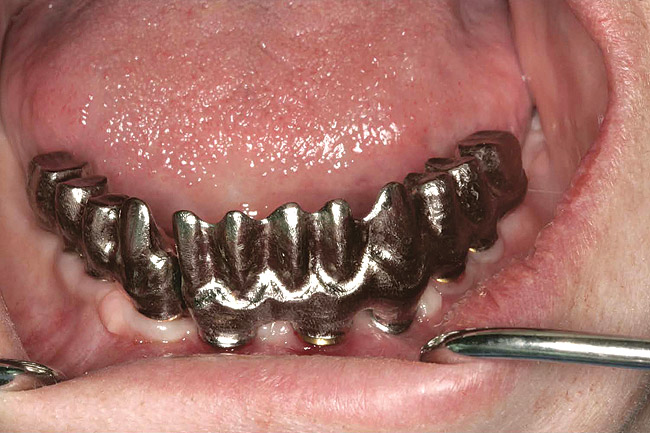

Figure 5  The increased amount of metal required for this prosthesis greatly increases the laboratory costs.

Figure 5

Figure 6  The increased amount of metal required for this prosthesis greatly increases the laboratory costs.

Figure 6

Figure 7   A hybrid restoration requires less metal to fabricate.

Figure 7

Figure 8   A hybrid restoration requires less metal to fabricate.

Figure 8